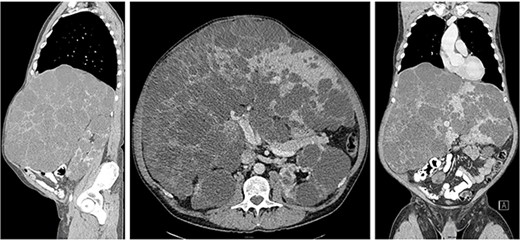

Over the years, the patient continued to experience an increase in abdominal girth. In the CT examination of 2017, the liver size was increased compared to the previous CT: the dimensions of the liver was 33 x 21 x 27 cm (Fig. 1). Considering the continued enlargement of the liver and worsening of symptoms, the patient was put on the waiting list for a liver transplant in the spring of 2019. Due to the lack of intensive care places during the COVID pandemic, he was temporarily off waiting list. Because of the worsening abdominal pain and malnutrition, markedly decreased exercise tolerance, the patient was again placed on the active waiting list for a liver transplant in May 2022.

Computed tomography showed extremely enlarged liver with the dimensions of 33 x 21 x 27 cm.